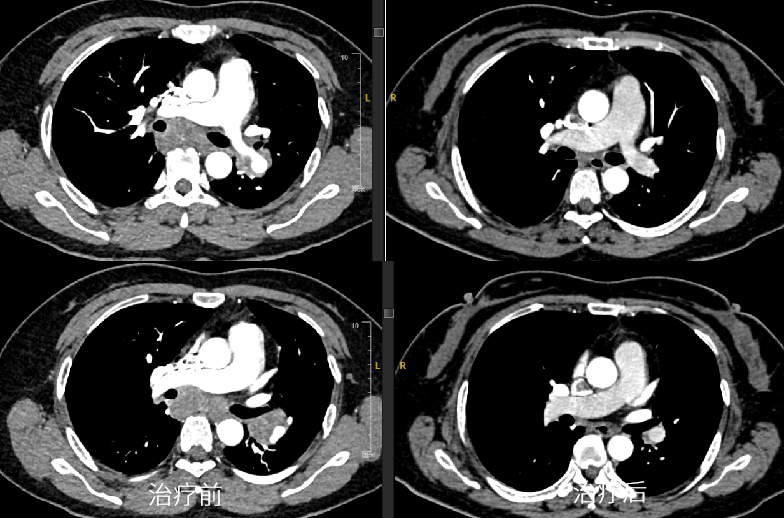

肺癌是严重威胁人民群众生命健康的恶性肿瘤,晚期肺癌患者已错失最佳手术时机,传统的化疗方案对于晚期肺癌患者的总体效果难以满足临床需求[1]。近年来,以PD-1/PD-L1抑制剂为代表的免疫疗法在肺癌治疗中的价值得到积极探索,我国自主研发的PD-1抑制剂替雷利珠单抗在肺癌领域也进行了广泛布局,目前已获批晚期非小细胞肺癌(NSCLC)一线及二/三线治疗适应症,且是唯一实现不可手术局晚及晚期NSCLC医保全程覆盖的PD-1抑制剂。 本期由中山大学孙逸仙纪念医院丁嘉萱医生为大家分享一例替雷利珠单抗用于晚期肺腺癌伴脑转移患者的诊疗过程,并由刘宜敏教授进行点评。该病例中,患者接受替雷利珠单抗治疗已实现超2年持续CR,目前免疫治疗已满两年,遂停止治疗,患者一般情况良好,后续定期影像学随访。 分享专家 丁嘉萱 医生 肿瘤学硕士 中山大学孙逸仙纪念医院放疗科医师 点评专家 刘宜敏 教授 病例详情 基本情况 一般情况:患者女性,53岁。 主诉:因“咳嗽伴气促4月,头痛半月”就诊。 现病史:患者咳嗽伴气促4月,头痛半月,于2020.05我院首诊。 既往史、个人史及家族史:无特殊。 月经婚育史:无特殊。 辅助检查 入院后基线评估: (1)胸部CT示:左肺门区可见一团块状影,大小约42.8mm*30.0mm,边界清,增强扫描呈轻度强化,强化尚均匀,病变包埋左下肺动脉,左肺下叶支气管狭窄,病变下缘可见子灶。纵隔内结构清楚,后纵隔内可见一团块状影,大小约52.8mm*21.0mm,边界清,强化方式与上述病灶相仿,与食管分界不清。双侧肺门淋巴结转移。 入院后胸部CT检查 (2)头颅MRI示:左颞叶、脑干见结节状稍长T1、稍长T2信号影,DWI呈稍高信号,增强后明显强化,周围见片状水肿影,直径分别为8.7mm和11.2mm;左颞叶、脑干异常信号灶,结合病史,考虑转移瘤;全腹MR和全身骨显像无明显异常。 入院后MRI检查 (3)超声支气管镜引导下的经支气管针吸病理活检(EBUS-TBNA):1、左上叶下舌段支气管及左下叶背段支气管,左下叶基底段支气管管腔外压性狭窄;2、隆突增宽;3、纵隔淋巴结转移(第7组,第11L组),EBUS-TBNA细胞病理提示为肺来源腺癌。 于左侧第二隆突探及第11L组淋巴结行EBUS-TBNA (4)免疫组化:TTF-1(+)、NapsinA(+)、CK7(+)、CK5/6部分(+)、Ki67约25%(+),P40(-),PD-L1(22C3)肿瘤细胞约30%(+)、PD-L1(22C3)免疫细胞约20%(+)。 (5)基因检测:RET基因重排。 临床诊断 左肺腺癌伴脑转移(T4N3M1c,IVB期);RET基因重排 诊疗经过 于2020.06.01、2020.06.22、2020.07.13、2020.08.04、2020.08.25、2020.09.15予替雷利珠单抗200mg+培美曲塞800mg+奈达铂110mg治疗6周期;期间于2020.06.04-2020.07.13行WBRT(37.5Gy/15f)+SRS(14Gy),WBRT同期给予替莫唑胺(75mg/m2)。 免疫治疗2周期后复查胸部CT提示:左肺门区肿块较前缩小(21*14mm),后纵隔淋巴结较前缩小(22mm*9mm),左颞叶病灶基本消失、脑干病灶明显缩小(5mm),水肿明显消退。疗效评估为PR。免疫治疗4周期后复查胸部CT,疗效达到CR。 治疗前vs. 免疫治疗2周期后复查胸部CT结果对比 治疗前vs. 免疫治疗2周期后复查胸部CT结果对比 治疗前vs. 免疫治疗4周期后复查胸部CT结果对比 后暂停免疫联合化疗,于2020.09.17-2020.10.30行肺癌累及野放疗(pGTV、pCTV:60Gy/30f)。后于2020.11.12-2022.08.25行替雷利珠单抗200mg+培美曲塞500mg维持治疗23周期。期间定期影像学随访(外院),疗效维持CR。 2021.11.17胸部CT提示:左肺下叶背段及左肺上叶近肺门区团片状密度增高影,其内支气管稍扩张,邻近胸膜可见增厚,同前大致相仿。右肺上叶纵隔旁至近肺门区亦见条片状实变影,部分沿支气管分布,局部支气管稍扩张;右肺中叶内侧段见少许条状影,同前大致相仿。少量心包积液较前稍增多,新见双侧胸腔少量积液。纵隔内见多枚小淋巴结。附见肝右叶后段低密度灶部分向外突出,肝脏余部另见低密度小结节,十二指肠降段见含气囊袋影,同前大致相仿。 2021.12.16头颅MRI(平扫+增强)提示:脑桥右侧区见一小条片异常信号影,T2W1及FLAIR上呈稍高信号,信号较前减低,T1W1上显示欠佳,增强扫描现片未见明确强化,余颅内脑组织形态、信号正常,中线结构居中,脑室系统形态、大小正常,脑池、脑沟及脑裂未见异常,小脑未见异常信号。增强后脑组织强化正常,未见异常信号灶。附见:双侧筛窦及右侧上颌窦黏膜少许增厚。 2022.06.23 PET-CT检查提示:1、左肺癌治疗后,左肺下叶背段及左肺上叶近肺门区斑片状密度增高影伴轻度代谢增高,病灶较前明显吸收,代谢较前减低,考虑放射性肺炎较前吸收、好转,建议追踪复查;2、左侧肺门(10L)及纵隔内(4R、5、7 组)多个小巴结,代谢未见明显增高,结合病史,考虑为淋巴结转移灶治疗后处于明显抑制状态,建议追踪复查;3、脑转移瘤治疗后,颅脑未见明显提示脑转移瘤的高代谢灶,结合病史,考虑脑转移瘤治疗后好转,请结合MRI增强结果。 患者接受免疫治疗满两年(末次治疗时间为2022.08.25),疗效维持CR,与患者充分沟通后,停止免疫维持治疗,定期随访。 2022.11.22头颅MRI(平扫+增强)提示:脑桥右侧区见一小条片异常信号影,T2W1及FLAIR上呈稍高信号,T2W1上显示欠佳,增强扫描未见明确强化,较前大致相仿。双侧顶叶及左基底节区异常信号灶。余颅内脑组织形态、信号正常,中线结构居中。脑室系统形态、大小正常,脑池、脑沟及脑裂未见异常。增强后余脑组织强化正常,未见异常信号灶。附见:双侧筛窦及上颌窦黏膜少许增厚。 2022.12.23胸部CT提示:双肺门区条片状实变影较前缩小、变淡,局部支气管通畅,增强扫描未见明确异常强化灶;右肺中叶内侧段见少许条状影,同前相仿。心包未见积液。纵隔及肺门未见肿大淋巴结;双侧胸腔未见积液。附见肝右叶后段低密度灶部分向外突出,最大横断面约4.4*2.5厘米,增强扫描呈早出晚归强化特点。肝脏余部另见低密度无强化小结节。十二指肠降段见含气囊袋影。 病程回顾 病例点评 该患者在完善相关检查后,最终被确诊为“左肺腺癌伴脑转移、后纵隔与双侧肺门淋巴结转移”。肺癌起病隐匿,约10%-25%的NSCLC患者在确诊时已发生脑转移,约50%的患者在疾病进展中发生脑转移[2]。肺腺癌作为NSCLC的主要病理类型之一,其发病率近年来持续上升[3]。 肺癌脑转移患者的死亡率很高,传统的治疗手段疗效非常有限。数据显示,在未接受治疗的脑转移患者中,中位OS仅为1个月,而接受最佳支持疗法的患者OS约为2个月[2]。近年来,免疫药物及靶向药物的研发问世,大大提高了肺癌脑转移患者的生存率。该患者PD-L1表达阳性,一项汇总分析结果显示[4],对于PD-L1 TPS≥1%的NSCLC脑转移(包括未经治)患者,相比单纯化疗,免疫治疗可改善治疗结局,同时具有更少的不良事件。 有研究表明[5],免疫联合放疗不仅可控制照射区原发肿瘤增殖,同时也能促进肿瘤组织释放抗原形成原位灭活疫苗增加免疫治疗疗效。在一项研究报道中,NSCLC脑转移患者接受免疫联合立体定向放疗安全性良好,不仅降低照射野外复发率,还可提高患者生存期[6]。此外,基因检测提示该患者存在RET基因重排,但我国首个高选择性RET抑制剂获批时间为2021年3月,在该患者2020年6月开始接受治疗时靶向药物暂不可及。 证据显示,免疫联合化疗具有协同增效作用[7],结合该病例具体情况及循证医学证据决定采用免疫联合化疗进行治疗。考虑到该患者为异地就医,为有效管理,提高患者依从性,需选择半衰期长的免疫药物,而我国自主研发的PD-1抑制剂替雷利珠单抗终末半衰期约为26天,达到同类药物最高范围,经MDT讨论予替雷利珠单抗联合化疗,并行WBRT+SRS(WBRT同期给予烷化剂)。近年来,替雷利珠单抗全面布局肺癌领域,积累了丰富的循证医学证据。 RATIONALE 304[8]为一项III期、多中心、随机、开放研究,旨在对比替雷利珠单抗联合化疗和单用化疗一线治疗晚期非鳞状NSCLC的疗效和安全性。在2022 ESMO IO大会上,RATIONALE 304研究公布了最新数据,中位随访16.1个月后,替雷利珠单抗联合化疗组的mPFS进一步延长至9.8个月,显著降低37%的疾病进展风险,ORR达到57.8%,其中CR率提升至4.9%,约为对照组的3倍;mDOR进一步提升至10.6个月,患者获益持久。同时,该研究在此次大会上首次更新了OS数据,联合治疗组的mOS达到21.6个月,HR为0.68,显著降低32%的死亡风险。此外,在RATIONALE 304研究[9]的事后分析中,首次探索了免疫治疗联合化疗的至缓解时间分布,旨在充分了解免疫治疗的反应特征、最大化免疫治疗的临床获益提供了全新思路。结果显示,替雷利珠单抗联合化疗治疗有近50%的应答者在第二次评估后(≥4周期治疗后)出现首次缓解,提示若首次肿瘤评估未达到肿瘤缓解,不必急于停药,继续治疗仍很有可能达到缓解;75%达到CR/PR的患者通过持续治疗,肿瘤会持续退缩,首次缓解到最大肿瘤缓解的中位时间为3.6个月(约5个周期),肿瘤缓解深度更深的应答者,其PFS有延长的趋势,提示已达到CR/PR的患者,持续治疗肿瘤可进一步缩小,实现更长PFS获益。 患者在接受替雷利珠单抗联合治疗2周期后快速达PR,4周期疗效达到CR。6周期后暂停免疫治疗,在针对肺癌累及野放疗后,继续予免疫联合化疗维持治疗23周期,考虑到患者耐受性,在保证疗效的基础上化疗药物(培美曲塞)由标准剂量减量至500mg,以提高生活质量,期间影像学随访疗效维持CR。该患者共接受替雷利珠单抗治疗29周期,截至发稿已实现超2年长生存,充分验证了其在真实世界中用于肺腺癌脑转移患者的有效性和安全性。 根据2020年V1版《NCCN 非小细胞肺癌临床实践指南》,如果患者一线应用免疫疗法,则应接受两年的免疫维持治疗[10],具体临床实践中免疫治疗满2年后继续用药也可持续获益。该病例中,患者自2020年6月开始免疫治疗,至2022年8月已满两年,与患者充分沟通后,停止免疫维持治疗。截至末次随访(2022年12月),患者一般情况良好,未来实现长期生存值得期待。 长期以来,生存期短、预后差的肺癌脑转移患者常被排除在临床试验之外,血脑屏障(BBB)及血液-肿瘤屏障(BTB)等特殊结构也给脑转移相关机制研究造成重重困难[2]。目前,免疫联合放疗还有许多亟待解决的问题,如疗效评价、治疗结合时机、放疗范围及剂量等[5]。期待在未来,该领域能有更深入的研究进展,造福万千肺癌脑转移患者! 参考文献: [1] 王渊, 谭盼, 等. 中国医院用药评价与分析. 2023,23(03). [2] 马力, 朱娅, 等. 中国医药导报. 2023,20(03). [3] 李芳, 韩采利, 等. 肿瘤防治研究. 2023,50(03). [4] Aaron S Mansfield, et al. JTO Clin Res Rep. 2021 Jul 1;2(8):100205. [5] 周冲, 韩亮, 等. 中华转移性肿瘤杂志,2022,05(4):340-343. [6] Kamran A Ahmed, et al. J Neurooncol. 2017 Jun;133(2):331-338. [7] 赵景景, 李玲, 等. 实用癌症杂志. 2022,37(06). [8] Shun Lu, et al. ESMO IO 2022: 138P. [9] Lu S , et al. CSCO 2022. [10] NCCN Guideline NSCLC 2020.V1.